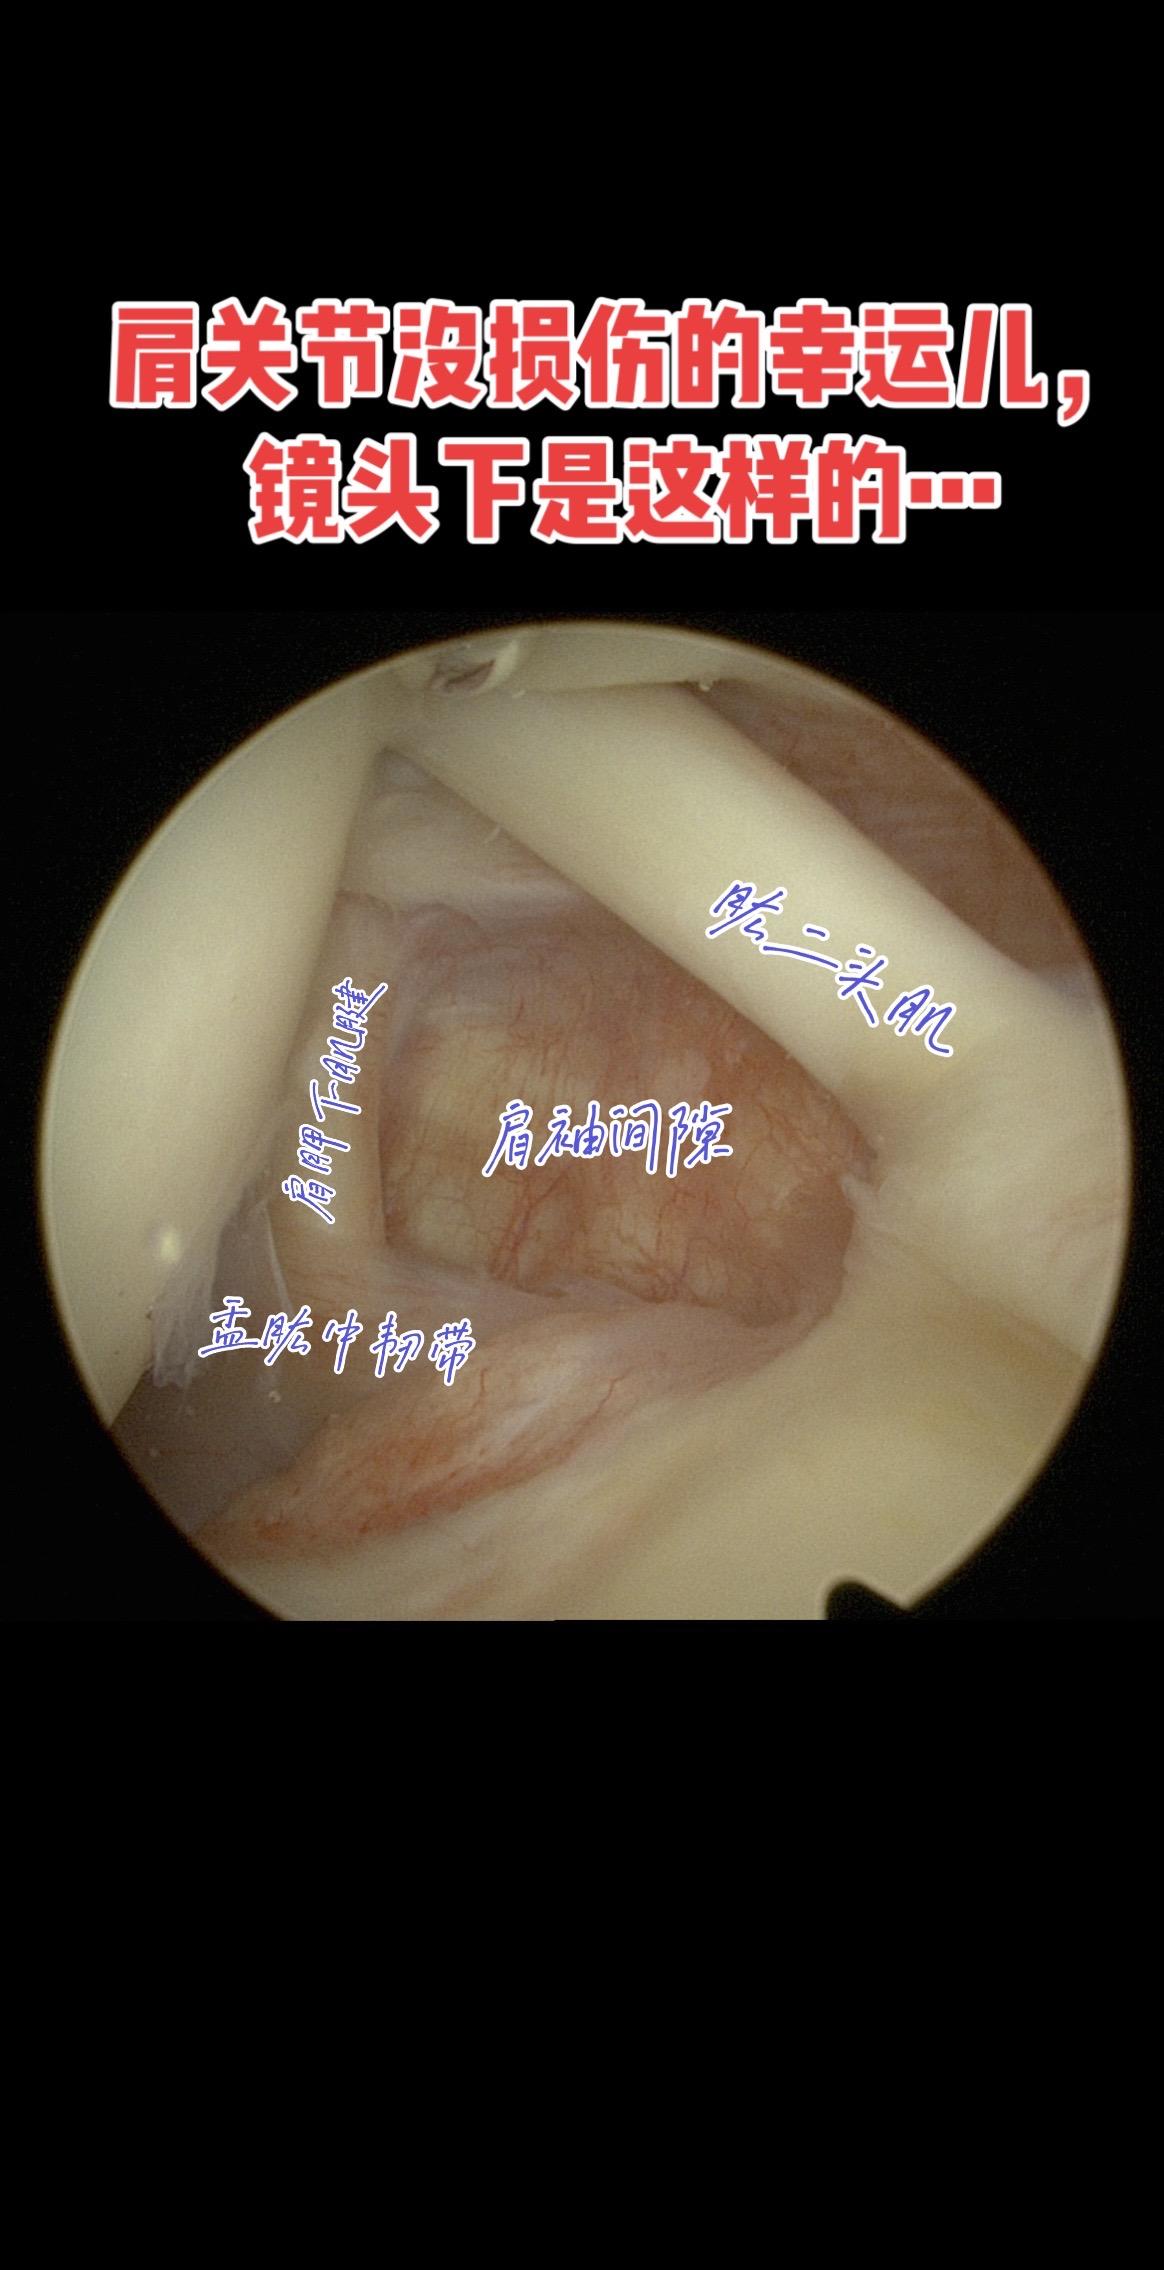

关节镜下的“完美肩关节”长啥样。肩关节肩袖